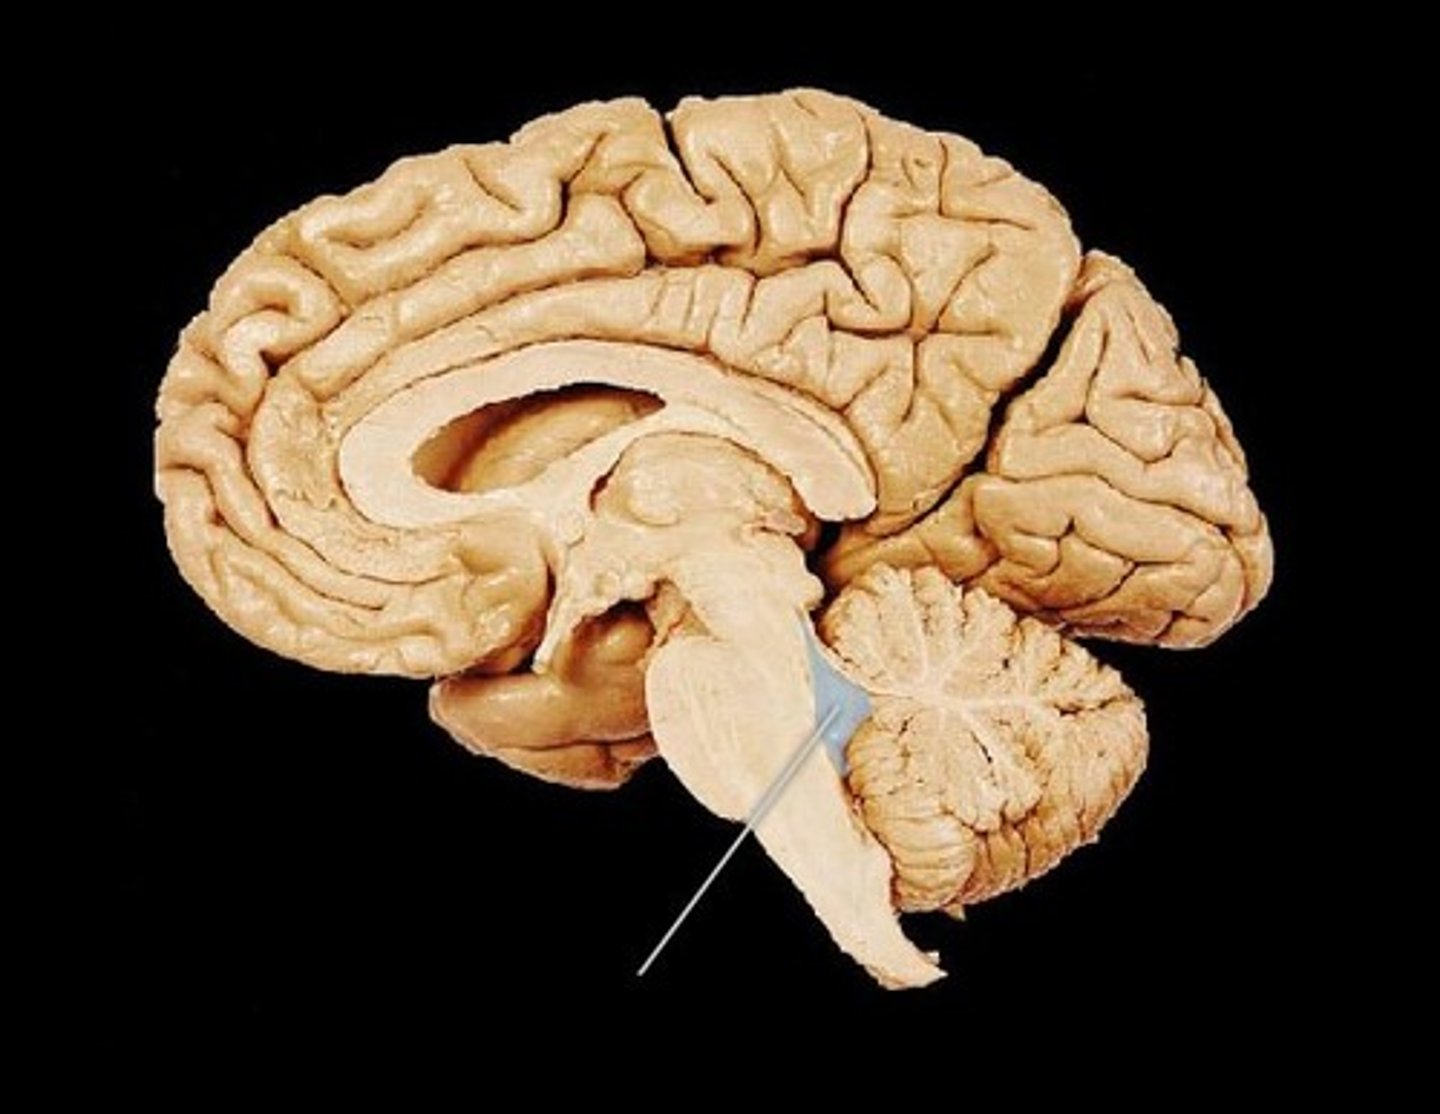

4th ventricle

midbrain

pons

medulla oblongata

cerebral aqueduct